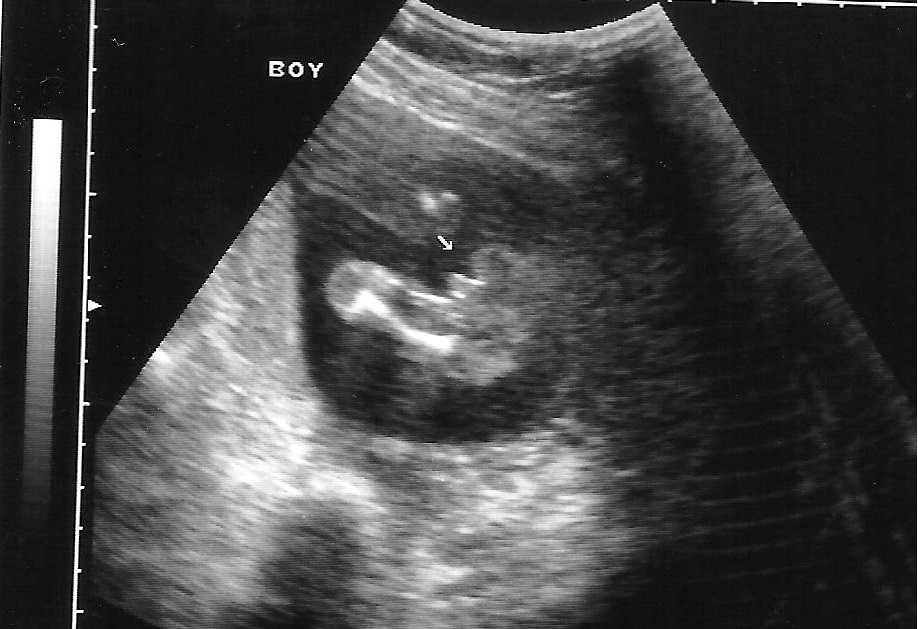

They can be wrong. However, I've had 2 ultrasounds since 20 weeks and both were very obvious boy parts so I'm not worried. As the nurse told me, those things don't usually fall off.

M born 1/6/09 - A born 12/31/10 - baby BOY RCS 12/2/14